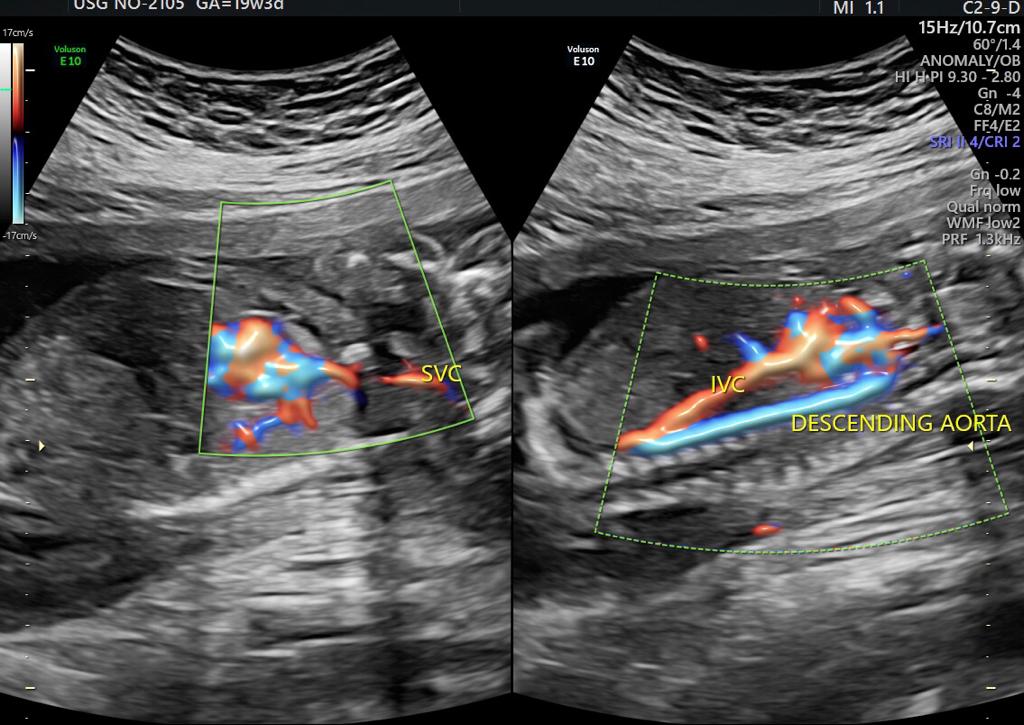

One of the most important scans done during pregnancy is during the second trimester, between weeks 18 and 20. This is called the targeted anomaly scan and is essentially a complete head to toe analysis of the fetus in a clinical perspective. Even though the scan might not be able to identify every single issue, however, gynaecology specialists in Guntur use this scan to validate and rule out any discrepancies with respect to most of the major organs in the Childs body including the brain, kidneys, bones, heart as well as the spinal cord and face, etc. The measurements with respect to every organ are taken also another important aspect of this scan is to identify how the placenta is placed and if it is tending towards creating an issue later on. Visit ultra sound test centers in Guntur at fertility hospitals.

Sometimes improper growth could be a cause of concern and on the other side, there are certain disorders which are identified in this scan, some could be rare congenital heart anomalies related to fetalbrain,face, thorax,heart,GIT,renal, skeletal etc